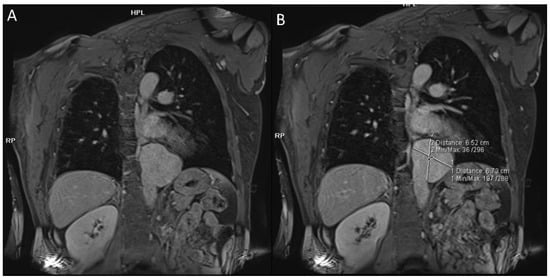

- Akpolat, T.; Danaci, M.; Belet, Ü.; Erkan, M.L.; Akar, H. MR Imaging and MR Angiography in Vascular Behçet’s Disease. Magn. Reson. Imaging 2000, 18, 1089–1096. [Google Scholar] [CrossRef]